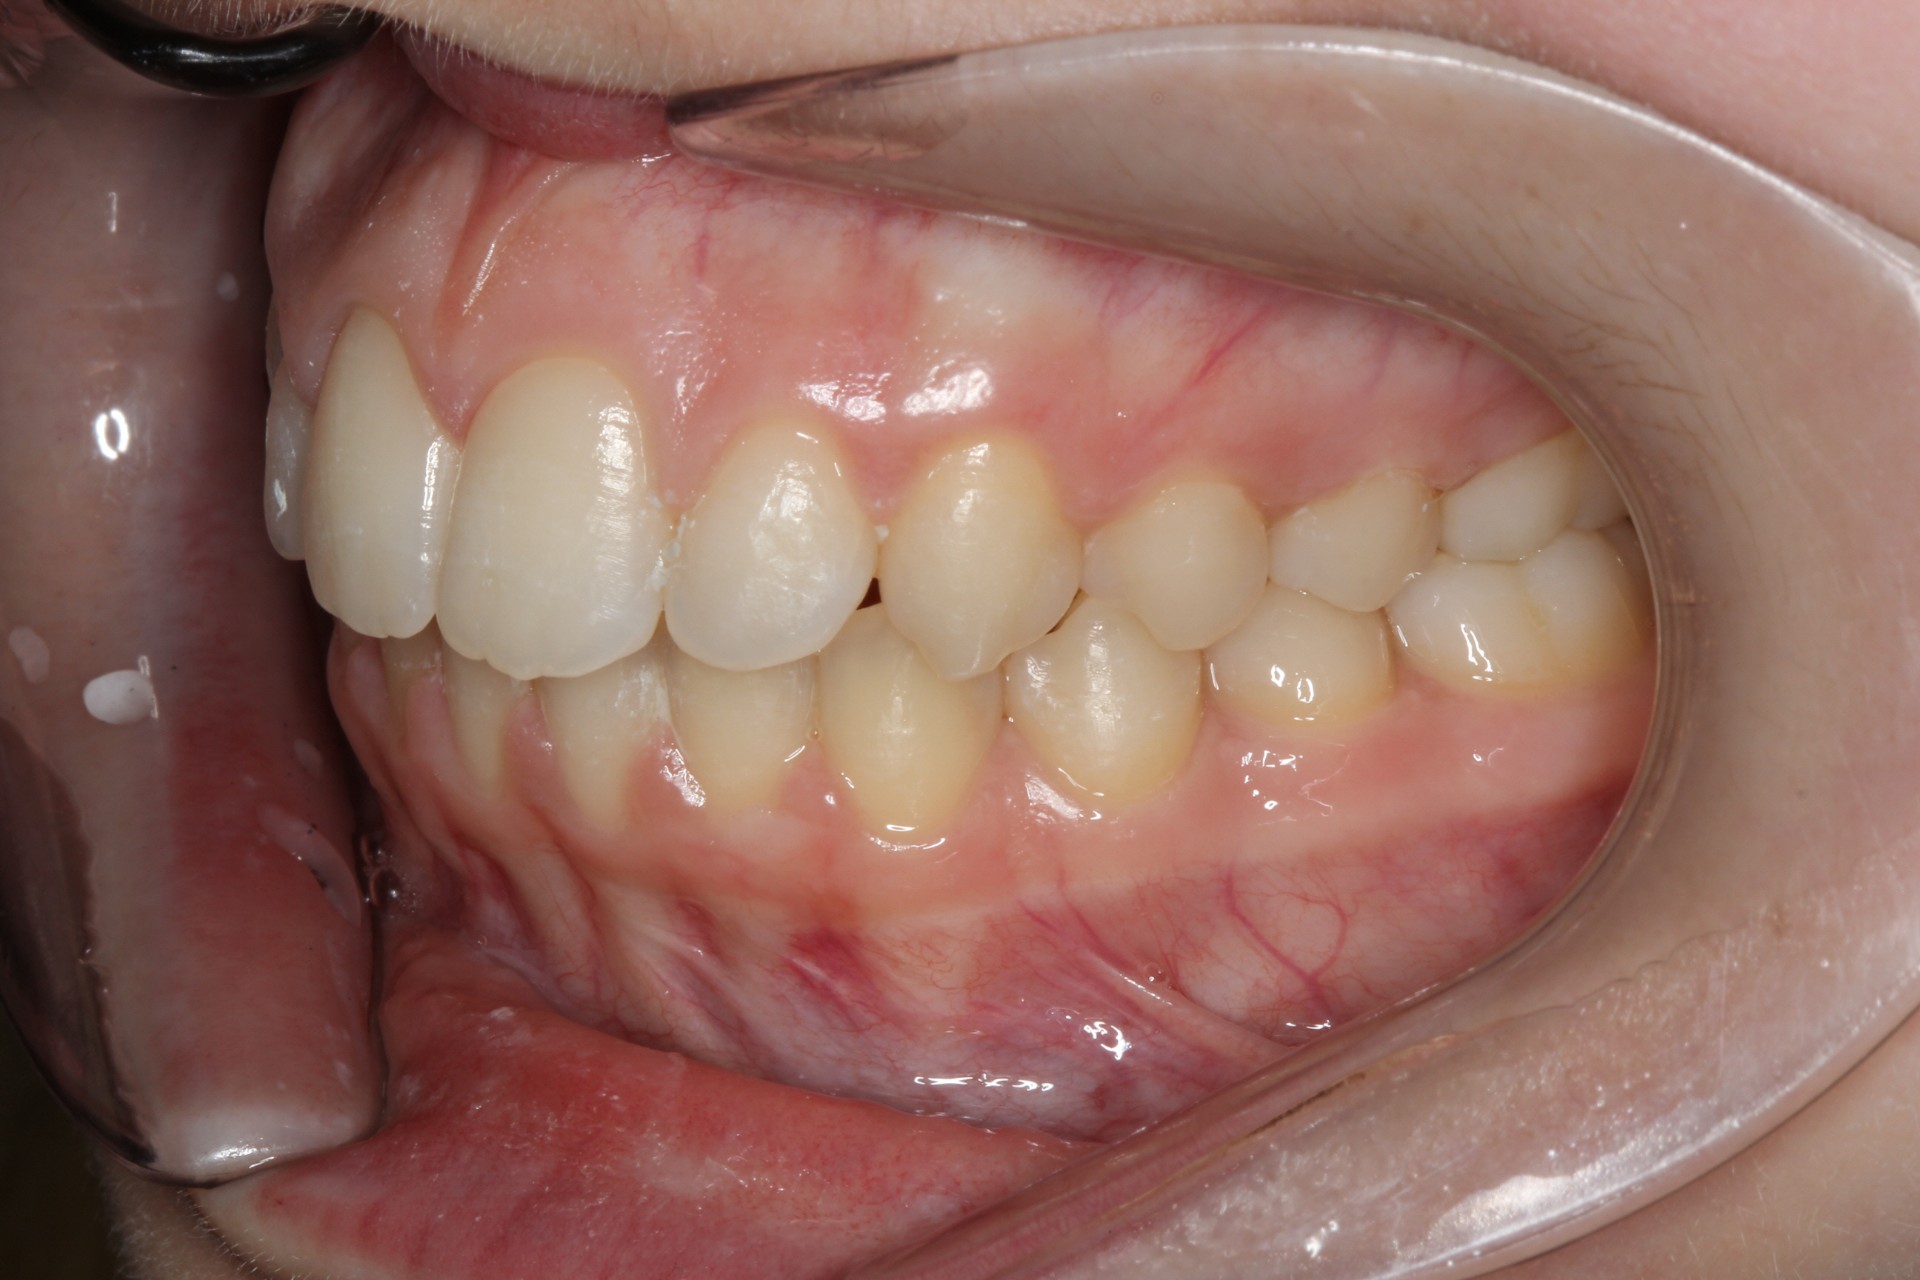

Crowding with lateral open bite – Child case